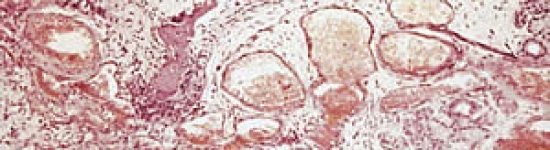

Rhinite Atrophique : Vacciner, c'est bien...bien vacciner, c'est mieux !